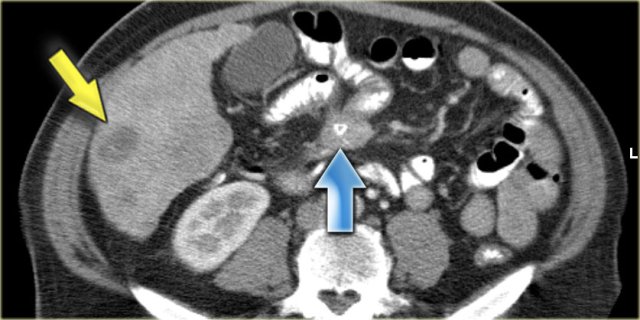

Carcinoid

Carcinoid is a slow-growing neuroendocrine tumour most commonly found in the small bowel.

Less than 10% of patients with carcinoid will develop the carcinoid syndrome, caused by the overproduction of serotonin, which can lead to symptoms of cutaneous flushing, diarrhea and bronchoconstriction.

Carcinoid metastasizes to the mesentery, which at times is easier to appreciate than the primary tumor in the small bowel.

There is associated bowel wall thickening due to a desmoplastic reaction.

On the left a patient with a typical carcinoid with central calcification (blue arrow).

Notice the bowel retraction and wall thickening.

There is a metastasis in the liver (yellow arrow).

On the left another patient with a carcinoid.

The right image is the octreoscan, which is positive in 85% of carcinoids, so this can be a great help in the differential diagnosis.

In this case we can also detect liver metastases on the scan (blue arrows).

Notice that there is no activity of a primary tumor in the small bowel.

This is often the case because the primary tumor can be quite small.